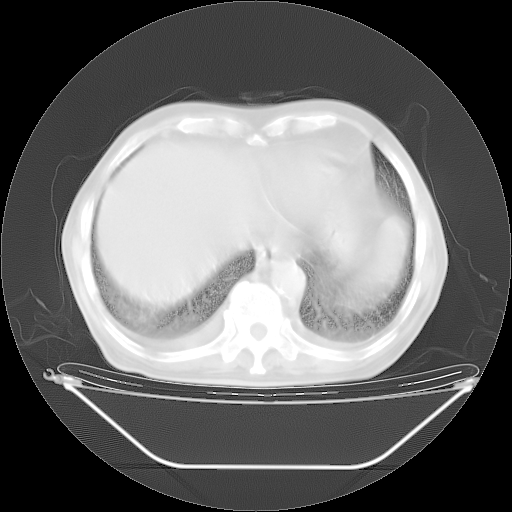

今天复查肺部CT,发现双肺广泛磨玻璃样改变。所以我把3月19日和5月9日相隔50天的肺部CT上传。请大家会诊。

2009年3月19日肺部CT片。

2009年3月19日肺部CT